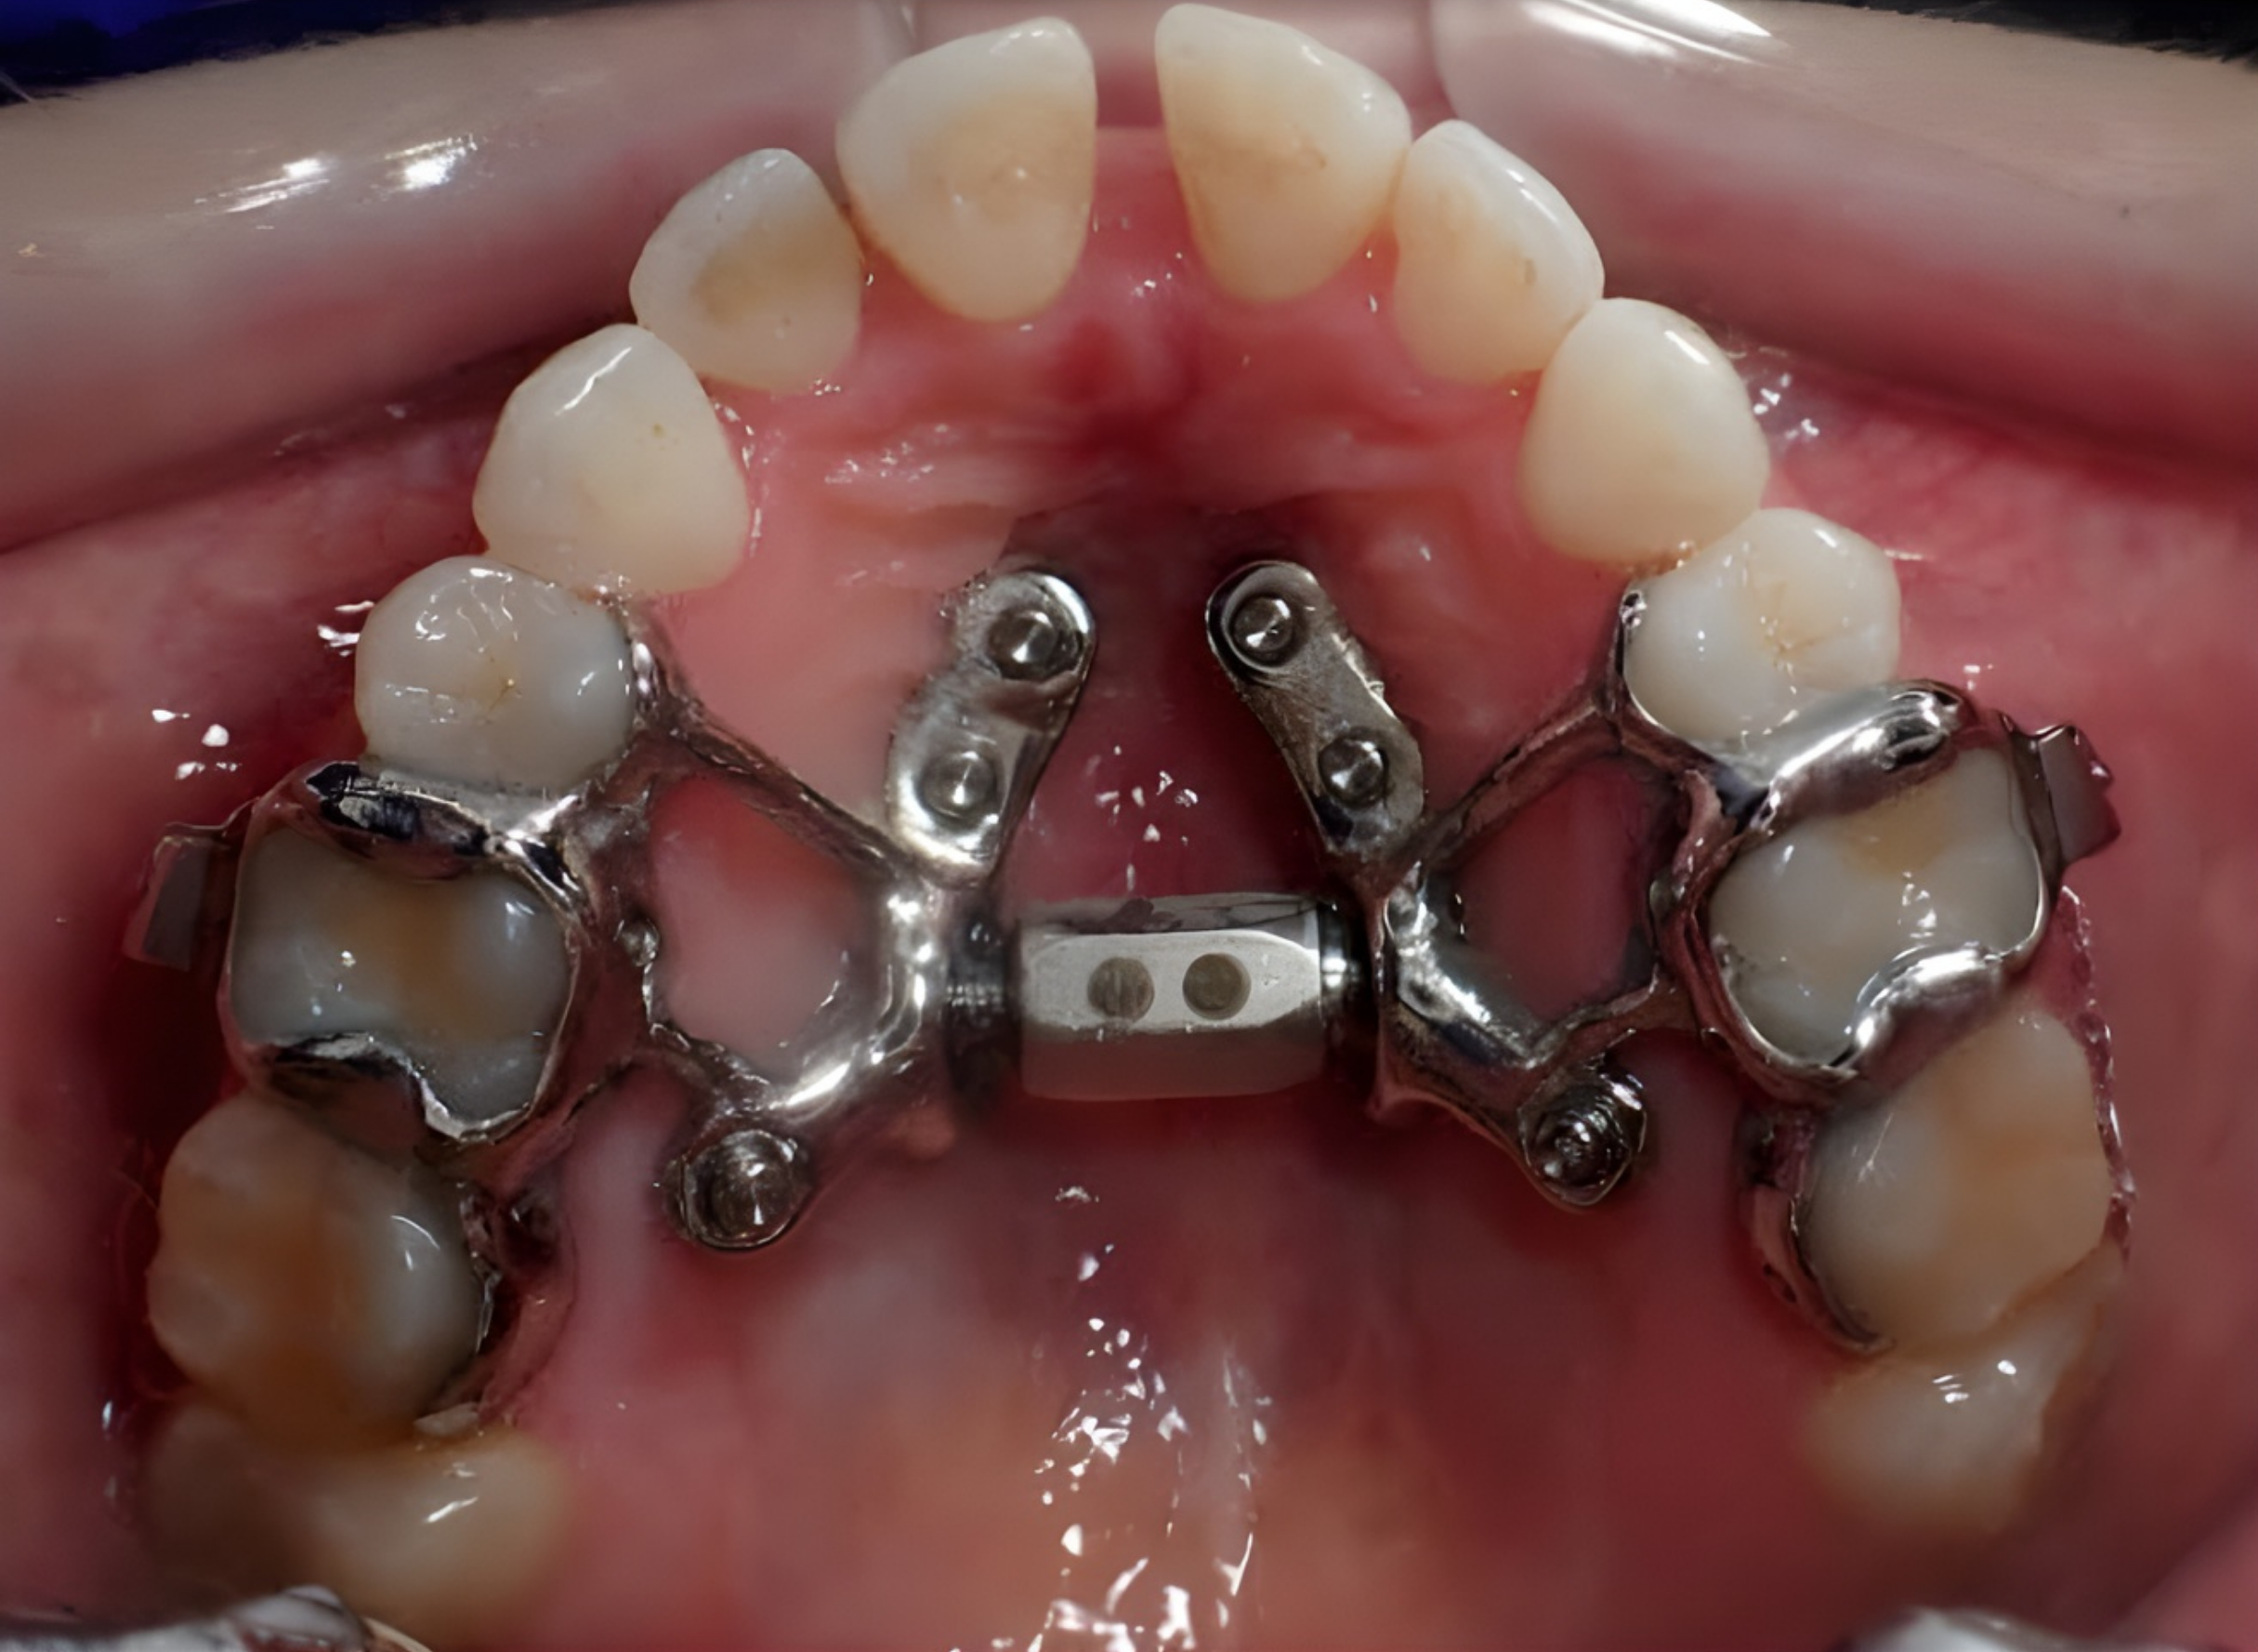

How Does MARPE Work?

MARPE (Mini-Implant Assisted Rapid Palatal Expansion) uses a specialized expansion device anchored directly to the bone using small temporary mini-screws (TADS). These implants provide skeletal support, allowing expansion forces to be delivered to the maxillary bone rather than the teeth alone. Over time, controlled activation of the appliance gradually separates the mid-palatal suture, encouraging new bone formation as the jaw widens. This process creates stable, orthopedic change while minimizing unwanted tooth tipping or gum stress. Patients or caregivers typically activate the appliance at home using a small key according to a customized treatment schedule prescribed by the orthodontist.

What Does Custom 3D-Printed MARPE Treatment Look Like?

Custom 3D-printed MARPE treatment begins with a digital workflow. A 3D scan of the patient’s teeth and advanced imaging are used to precisely design the appliance based on the individual’s anatomy. Using computer-guided planning, the exact position, angulation, and depth of each mini-implant are mapped before treatment even begins. The appliance is then fabricated using high-precision 3D printing technology, creating a device that fits the patient’s palate with exceptional accuracy. During placement, the custom design allows for efficient insertion and immediate stability, often resulting in improved comfort and predictable outcomes compared to traditional prefabricated expanders.